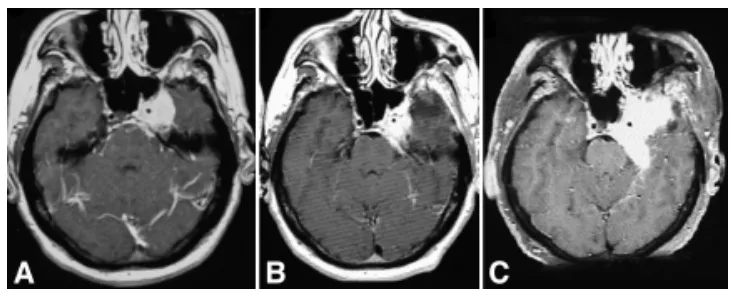

48岁男性患者,表现为完全性眼肌麻痹(第III、IV、VI对颅神经受累)伴三叉神经第一支分布区感觉减退。磁共振成像显示左侧中颅窝巨大强化占位(4.5×4.5×4.0厘米),累及海绵窦,压迫海绵窦段颈内动脉及蝶鞍,向前延伸至视神经管,向后进入左侧环池(图2A)。血管造影显示肿瘤压迫致左侧颈内动脉狭窄。经眶颧颧入路切除左侧海绵窦脑膜瘤过程中,因球囊闭塞单光子发射计算机断层扫描显示皮层灌注缺损,未对颈内动脉壁的侵袭性肿瘤进行激进切除。术后即刻MRI显示左侧海绵窦残留肿瘤大小为1.8×1.5×1.0厘米,9个月后增大至2.2×2.3×3厘米(图2B)。3年后随访MRI显示残留肿瘤生长,遂行放射外科治疗。放射外科治疗4年后,常规随访显示肿瘤显著增大至5.5×5.0×5.0厘米(图2C)。MR血管造影显示颈内动脉因肿瘤包裹而狭窄。患者经左侧眶颧颧开颅再次手术,显微镜下切除复发性脑膜瘤的颞颞下及颅内部分。患者术后无新增神经功能缺损,但左侧完全性眼肌麻痹未改善。